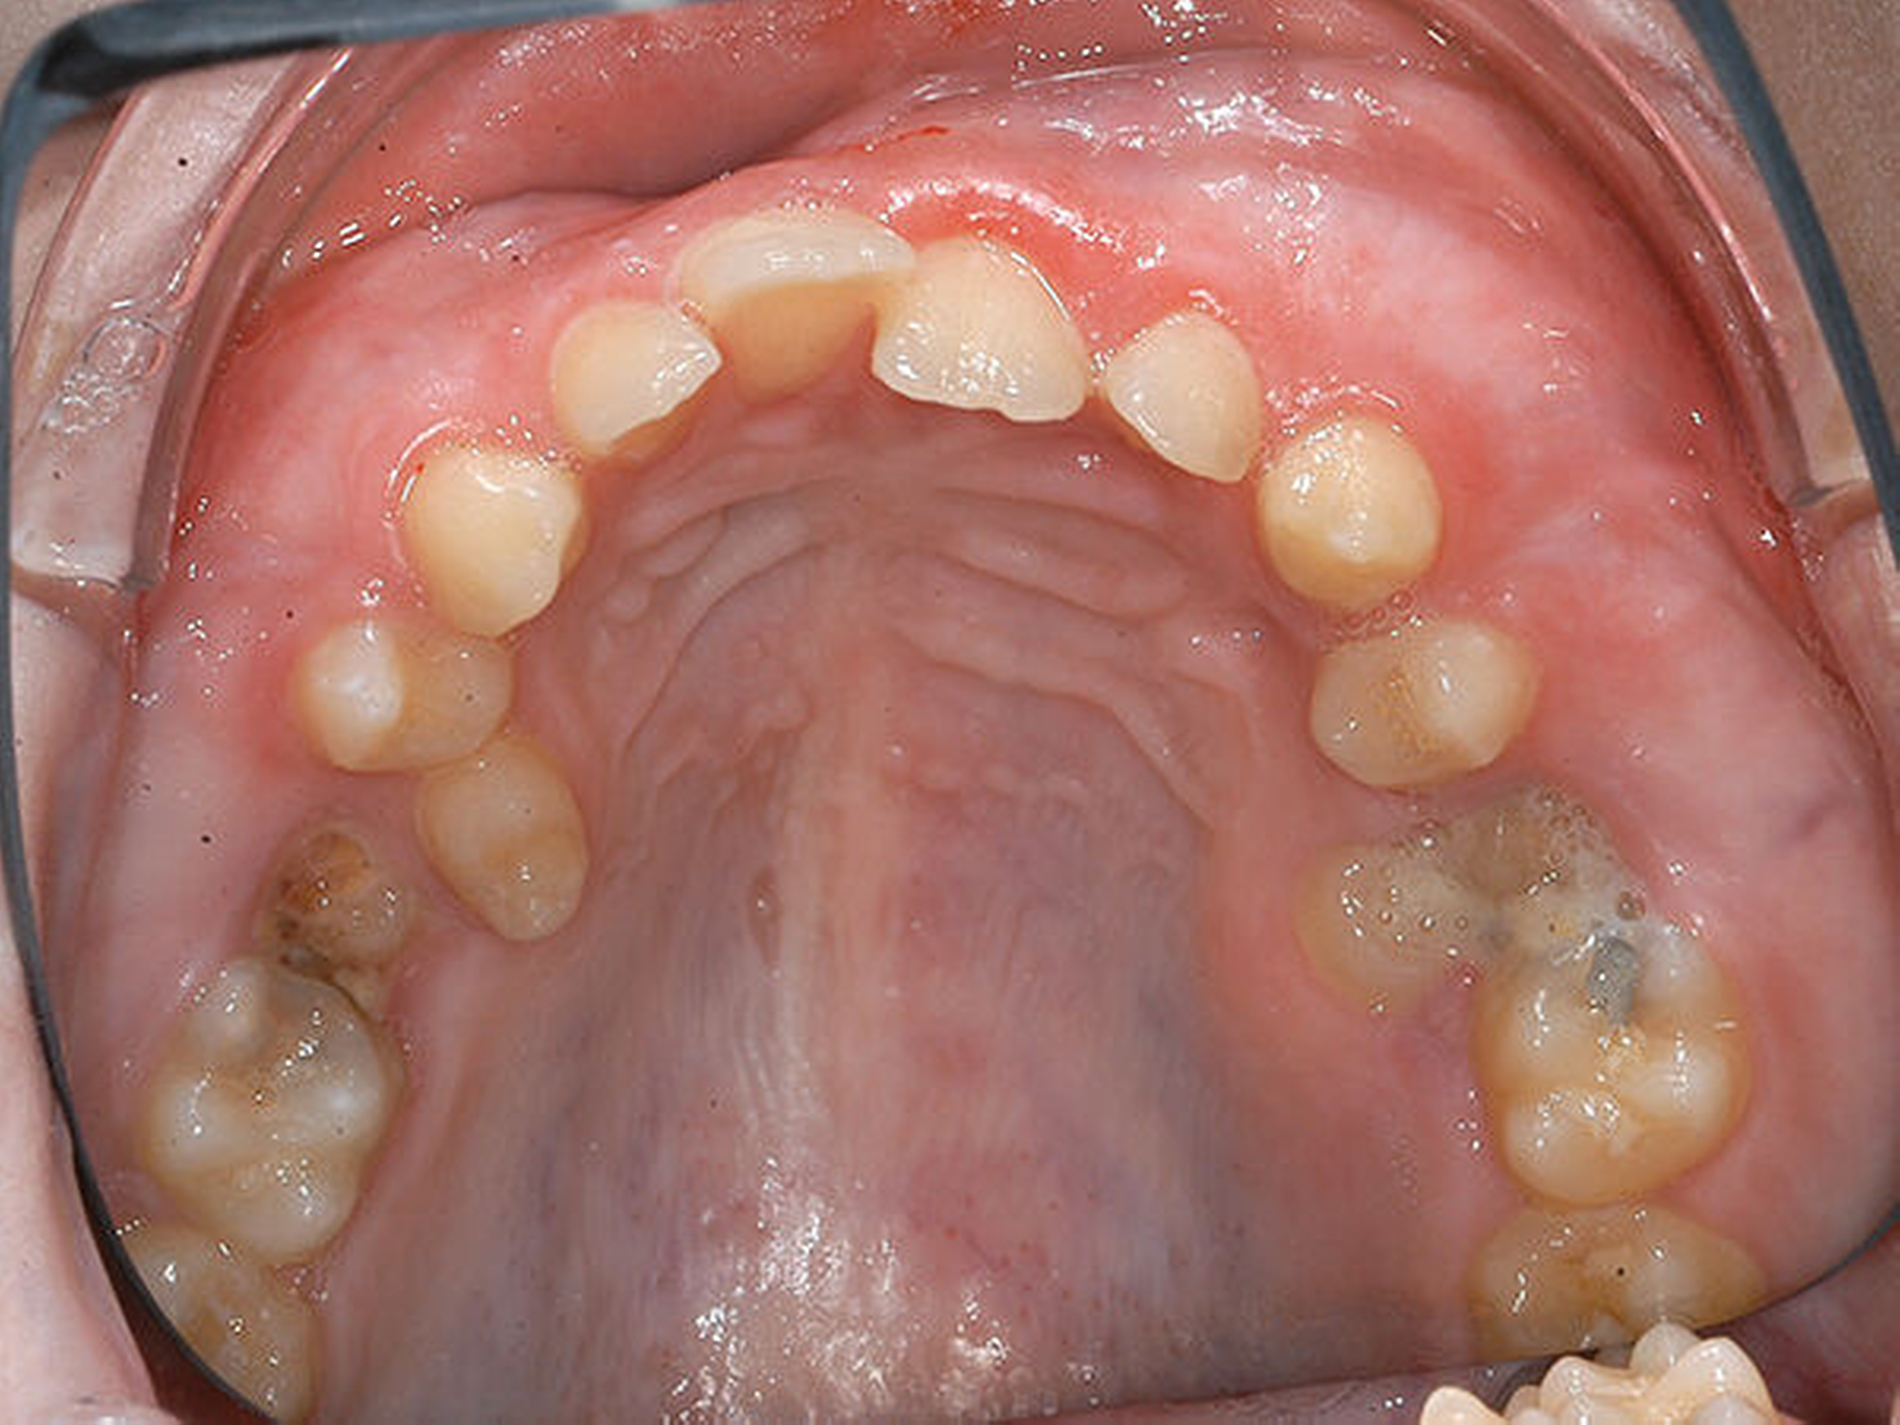

Eine 17-jährige Patientin wurde im Januar 2016 in der Spezialsprechstunde „Seltene Erkrankungen mit oraler Beteiligung“ in der Poliklinik der Klinik für Mund-, Kiefer- und Gesichtschirurgie am Universitätsklinikum Münster mit den noch persistierenden Milchzähnen 55 und 65 sowie einer kariösen Läsion mesial an 16 vorstellig. Die Prämolaren 15 und 25 waren nach palatinal durchgebrochen, im Bereich des persistierenden Milchzahns 65 trat Pus aus, der gesamte Oberkiefer erschien voluminös aufgetrieben (Abbildung 1).

Aufgrund der Pus-Bildung in regio 65, des palatinalen Durchbruchs der Zähne 15 und 25 sowie der kariösen Schädigung des Zahns 16 und der zu erwartenden weiteren Schädigung an 26 erfolgte die Entscheidung, die Zähne 55 und 65 zu entfernen. Die subgingivale, kariöse Läsion an Zahn 16 konnte nicht mehr restauriert werden, so dass auch dieser Zahn als nicht erhaltungswürdig eingestuft wurde und ebenfalls entfernt werden sollte.